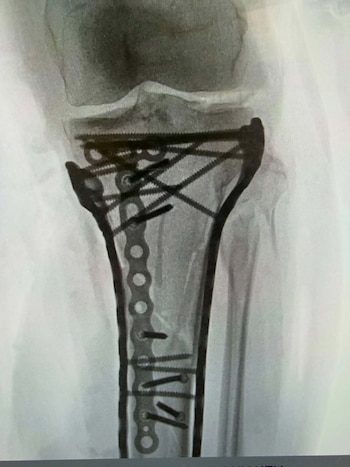

La recuperación de la ex campeona olímpica se presenta compleja. El doctor Bertrand Sonnery-Cottet, especialista en ortopedia y cirugía de rodilla, advirtió en declaraciones a RMC Sports que lesiones de esta naturaleza pueden derivar en amputación, aunque aclaró que en este caso se logró evitar ese desenlace. En imágenes compartidas por Vonn en sus redes sociales, se observan numerosas placas y tornillos en la pierna intervenida, acompañadas por el mensaje: “Ahora soy biónica de verdad”, en tono irónico.